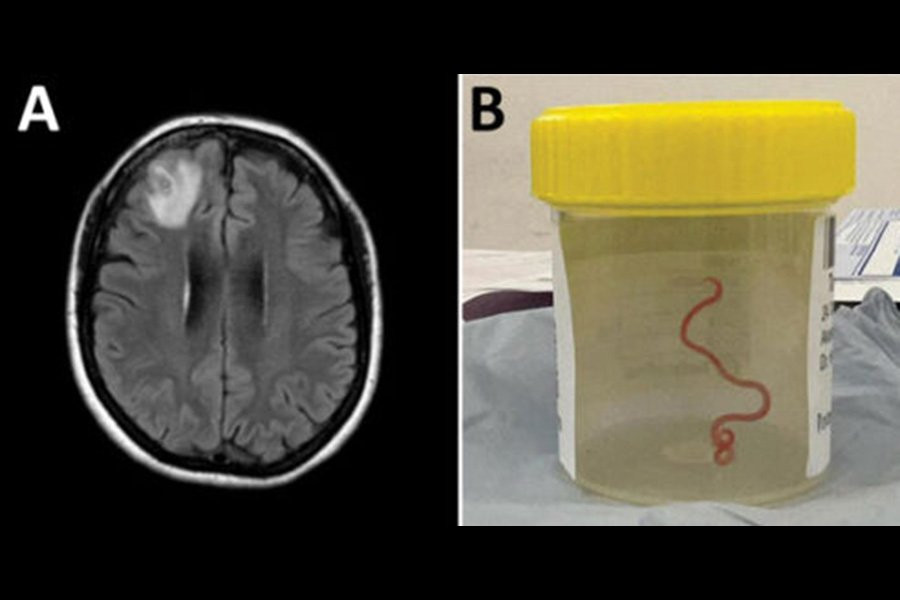

Во время операции на открытом мозге 64-летней женщины врачи больницы Канберры заметили длинную, похожую на струну структуру внутри поражения, поражающую ее правую лобную долю. Вытащив его, они поняли, что это живой извивающийся круглый червь. Тематическое исследование было опубликовано в журнале Emerging Infectioushoods.

Сканирование мозга выявило поражение правой лобной доли, потребовавшее хирургического вмешательства. Именно здесь нейрохирурги обнаружили паразита, крадущегося во взрослой форме.